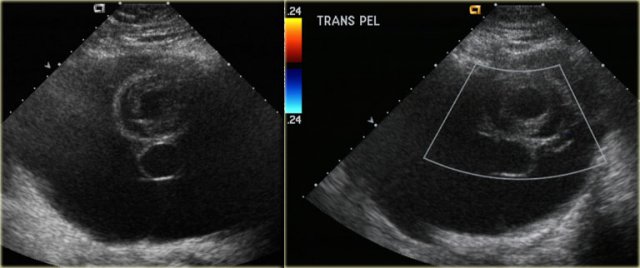

The normal ovary in pre-menopausal women contains small cysts.

The images show two normal ovaries with several anechoic, simple cysts consistent with Graafian follicles.

On T2-weighted MR-images the Graafian follicles are seen as bright cysts surrounded by darker solid ovarian stroma.